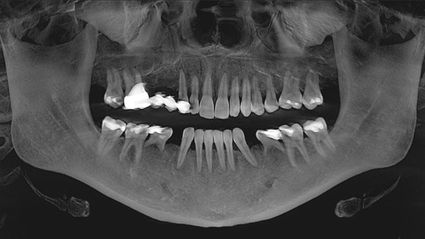

Ich wusste schon mein ganzes Leben lang, dass ich irgendwann Implantate brauchen würde, suchte aber nach einem Arzt, der meine Ziele mit der Optimierung meiner Gesundheit in Einklang bringen und einen individuelleren und "ganzkörperlichen" Ansatz bieten konnte. Auf einer Konferenz für funktionelle Medizin im Jahr 2016 lernte ich zufällig einen Arzt kennen, der mich an Dr. Volz verwies. Als ich im Oktober 2017 zum ersten Mal zu SWISS BIOHEALTH kam, hatte ich keine nennenswerten Gesundheitsprobleme, fühlte mich aber jeden Tag schrecklich müde, und obwohl ich meine Ernährung und meinen Lebensstil seit Jahren nicht verändert hatte, nahm ich langsam an Gewicht zu. Außerdem hatte ich ständig kalte Hände und Füße. Zusätzlich zu den 6 Implantaten, die ich benötigte, stellte Dr. Volz 4 Kavitationen fest und behandelte sie. Fast sofort hatte ich mehr Energie und war am Ende des Tages nicht mehr so müde.